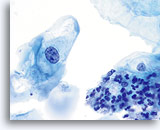

En raison de leur morphologie, les cellules issues de lésions de bas grade comptent parmi les anomalies intra-épithéliales les plus faciles à localiser et à identifier. En comparaison, les noyaux LSIL sont les plus grands et présentent un rapport N/C inférieur aux HSIL ou carcinomes. Ces cellules affichent une atypie nucléaire plus importante que les ASCUS (ce qui se traduit par une augmentation de la taille nucléaire, une irrégularité de la chromatine et une irrégularité de l’enveloppe nucléaire). Les noyaux peuvent occasionnellement ne pas être aussi hyperchromatiques que sur les frottis conventionnels, mais ils le sont toujours par rapport aux cellules normales environnantes. Les changements associés au HPV (par exemple, formation de cavités dans le cytoplasme) sont plus évidents grâce à la fixation liquide et à la technique de transfert, ce qui élimine la déformation des cellules associée à la méthode d’étalement conventionnelle. La méthode ThinPrep préserve mieux ces changements cellulaires, ce qui permet une meilleure distinction entre les véritables cavités cytoplasmiques induites par le HPV et les vacuoles bénignes/dégénératives et/ou les cellules malpighiennes glycogénées.

Comme il s’agit de cellules malpighiennes matures, elles gardent leur forme polygonale et conservent en partie leur taille normale. La taille des noyaux est au moins 3 à 4 fois supérieure à celle d’une cellule intermédiaire normale. En revanche, quand les changements associés au HPV sont évidents, les cellules peuvent être plus petites (quasiment parakératosiques), tout comme les noyaux (quelque peu pycnotiques) qui présentent en outre une binucléation et/ou multinucléation. Ces noyaux pycnotiques affichent en outre des caractéristiques anormales : hyperchromasie, augmentation de la taille par rapport à une cellule malpighienne superficielle normale, légère variation de la forme et de la taille, etc. Il est important d’insister sur le fait qu’une interprétation de LSIL/HPV implique des cavités cytoplasmiques nettes accompagnées de la morphologie nucléaire anormale décrite ci-dessus.